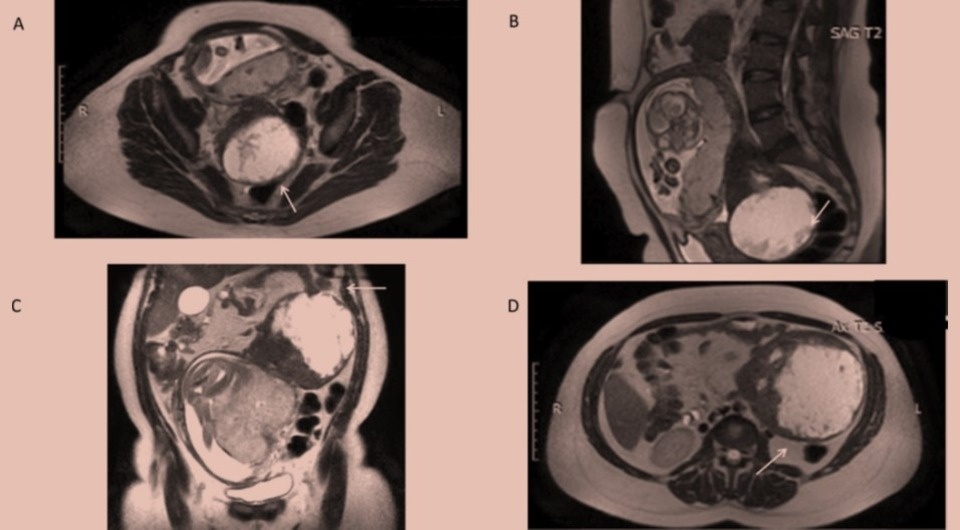

Верхняя опухоль на ножке имела размеры 18 × 12 × 7 сантиметров и простиралось от левой поддиафрагмальной области до дна матки. Нижнее образование размерами 9,5 × 8 × 8 сантиметров было тесно связано с задней стенкой матки. Уровень опухолевого маркера CA-125 был повышен, причем за две недели до этого он был в норме. Магнитно-резонансная томография показало толстые стенки у обоих новообразований и неоднородную жидкость в них.

Rosalba De Nola et al. / BMJ Case Reports, 2026

Бимануальное влагалищное исследование выявило еще одно неподвижное образование в Дугласовом пространстве размером около девяти сантиметров. Анализ крови указал на наличие железодефицитной анемии. При ультразвуковом исследовании врачи обнаружили два больших кистозных образования с ровными краями и периферической васкуляризацией.